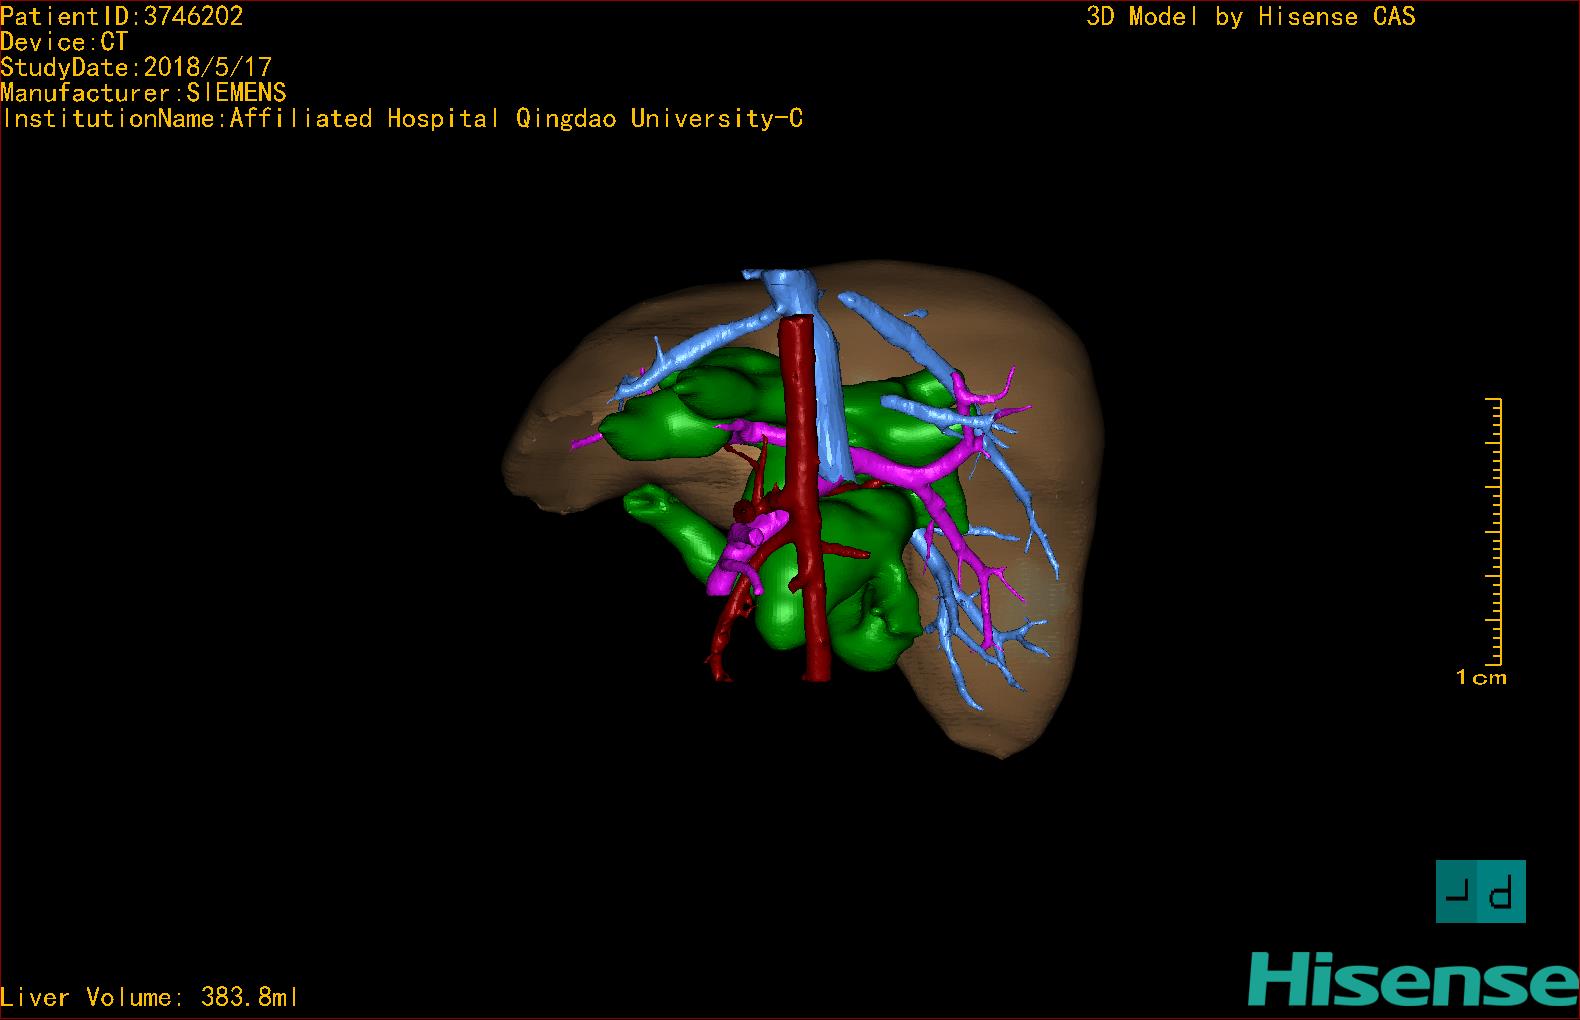

实验室检查: 血常规:血常规:WBC 11.49*109/L,NEU3.60*109/L,RBC4.36*1012/L,HB 119g/L, PLT 411*109/L,MCHC 318.0g/L, PCT 0.45%, RET% 1.64% 生化全套:ALT 18.00 U/L, AST 44.00 U/L, ALT/AST 0.41, ALB 47.35g/L,BIL-T 6.60 umol/L, BIT-D 2.68 umol/L, BUN 4.80 mmol/L, CREA 18.00 umol/L 肝炎全套: 炎症反应标志物: 诊疗过程: CT结果输入海信CAS系统后行3D重建及手术规划后,于2018-6-7全麻下行“胆囊切除+胆总管囊肿切除+肝总管空肠吻合术”手术治疗: 术前三维重建及手术方案设计: 将0.625mm双源薄层CT资料的静脉期和动脉期Dicom格式文件导入海信CAS系统。 通过调节窗宽窗位调整CT序号,对肝实质,胆囊,下腔静脉,肿瘤,肝动脉、门静脉及肝静脉等进行三维重建;系统自动计算肝脏体积,肝脏体积为383.8ml,通过术前模拟手术,精准判断手术切除范围,进行精密术前规划及讨论后实施手术。 手术步骤: 麻醉成功后,患儿取平卧位,2.5%碘伏消毒手术区皮肤,铺无菌巾单。取右上腹纵口长约5m,切开皮肤、皮下织组,腹直肌前鞘、腹直肌,后鞘和腹膜。探查见:胆总管3×2cm大小,胆囊管迂曲,长约10cm。剥离、切除胆囊,游离胆总管,将之横断:①近端即肝总管,剪裁后被吻合用;②远端游离切除囊肿内壁,直至胆总管开口于十二指肠处,冲洗后予以结扎缝扎。距treits韧带20cm处横断空肠:①近端与其远端25cm处的空肠侧壁行端侧双层吻合,吻合口通畅;②远端断端封闭,其侧壁剪开,并经横结肠后提至肝门处,与剪裁的肝总管行端侧双层吻合。缝合修补胆囊床及系膜裂孔,肝门部放置橡胶引流管一根。温盐水冲洗腹腔。检查无活动性出血,清点纱布器械无误,依次缝合腹壁各层。手术顺利,麻醉满意,出血不多,未输血,术后病人先进入麻醉恢复室,苏醒后回病房。手术时术者可开启Hisense CAS系统手势控制功能,对肝脏及胆囊解剖结构进行实时、全方观察、评估,起到术中导航作用。 术后病理: 1. (囊肿壁)囊肿性病变,囊壁构成于增生的纤维组织呈慢性炎,内衬假复层柱状上皮,囊壁内见较多增生的腺体。请结合临床。 2. 慢性胆囊炎。 随访情况: 患儿术后2周恢复良好 术前CT检查:动脉期

术前三维重建:重建图片.jpg)